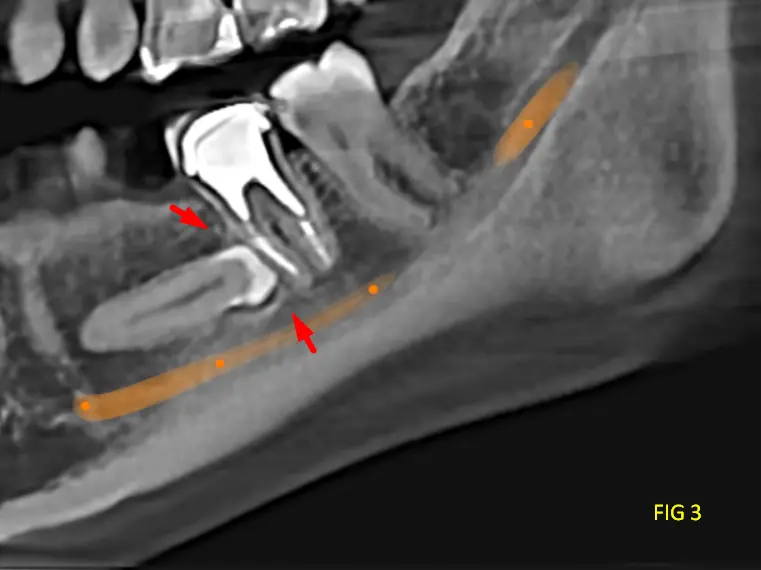

En las reconstrucciones 3D y cortes multiplanares (ver Fig 1, 2 y 3) se observa lesión oseteolítica extensa con ausencia de una capsula definida, ubicada en el cuerpo mandibular, lado izquierdo, zona de premolares.

Presenta tabiques óseos finos que delimitan compartimentos irregulares con expansión y adelgazamiento de las corticales óseas, con áreas de compromiso cortical. La relación cercana con el conducto dentario inferior, sin evidencia clara de invasión, pero con desplazamiento.

En cortes transversales se aprecia la naturaleza infiltrativa de la lesión, con forma de rayos de luz, sin límites netos, característica típica del mixoma Odontogénico.